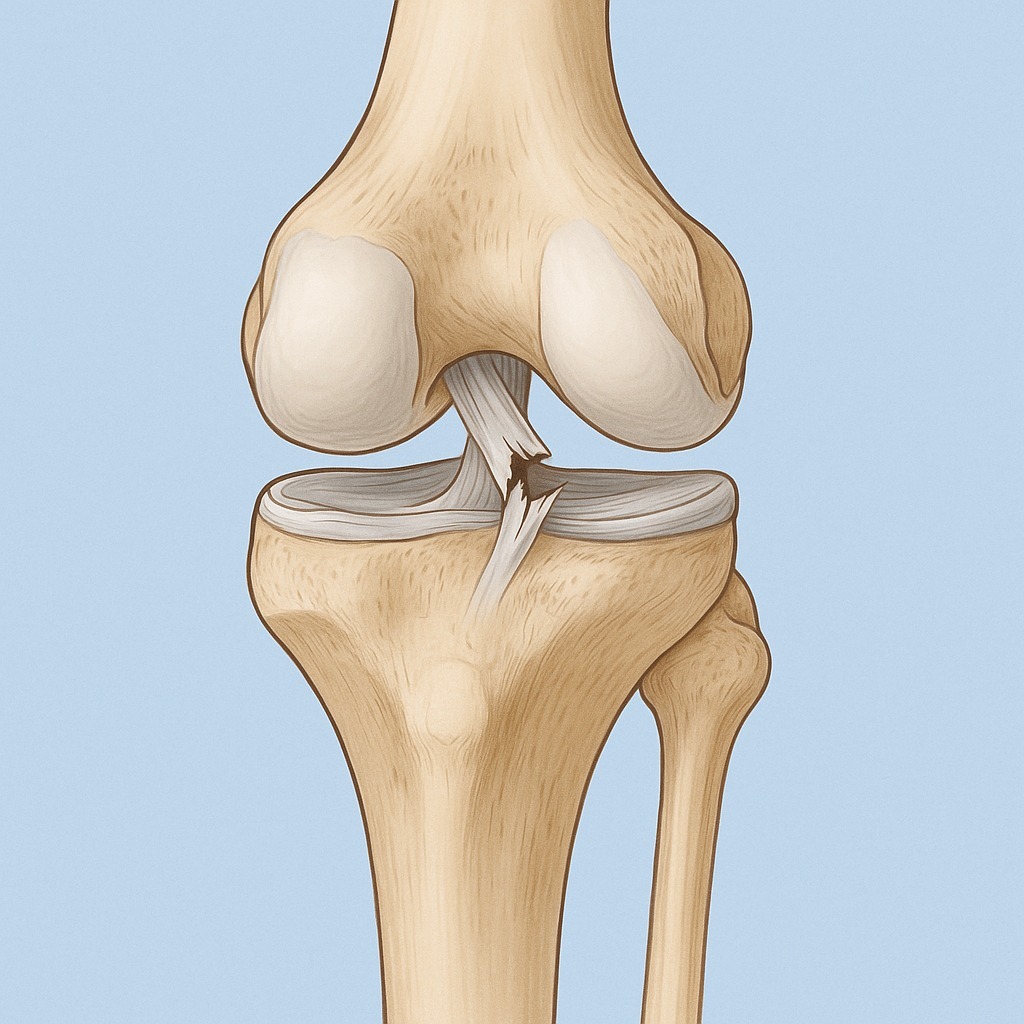

В этом треде обсуждаем разрушение суставов. Коленей, тазобедренных, плечевых, локтевых. Любых.

Остеоартроз – заболевание суставов, характеризующееся дегенерацией (разрушением) их хрящевой ткани и других структур, образующих сочленение – субхондральных (подхрящевых) частей кости, капсулы, синовиальной оболочки, связок, мышц. Хрящевая ткань, покрывающая суставные поверхности, истончается и разрушается, уменьшается количество синовиальной жидкости – возникают боль, отечность, деформация сустава. Выздороветь от этой патологии нельзя – восстановить разрушенный хрящ невозможно. Своевременная верификация болезни и адекватное лечение помогут замедлить прогрессирование патологического процесса и надолго сохранят качество жизни пациента.

Данные по артрозу разнятся. Чаще всего им страдают женщины, но у мужчин он появляется раньше. До 45 лет у 2-3%, что скорее генетическое, после 45 лет у 30%, после 60 лет у 60-80%.

В молодом возрасте артроз может возникать в следствии травм.